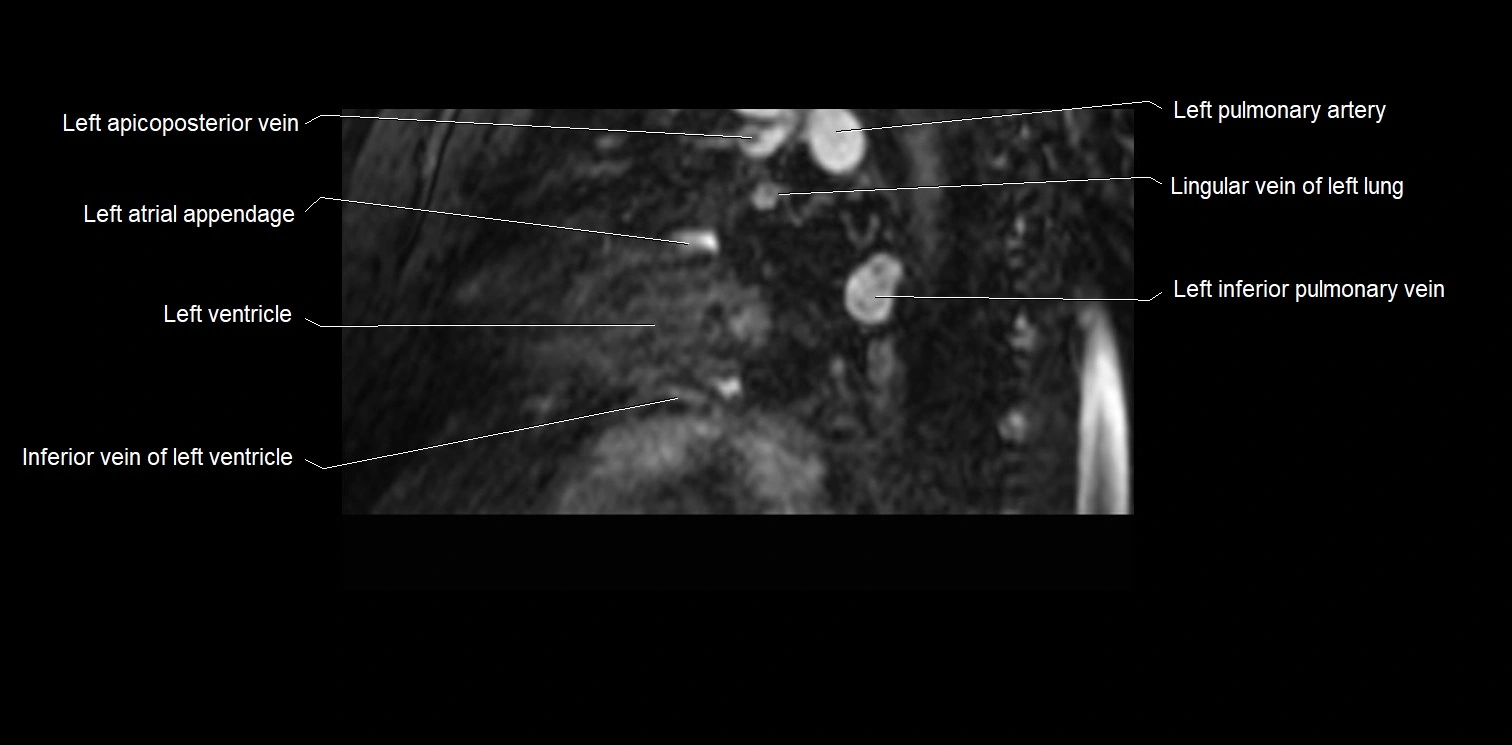

- Left inferior pulmonary vein

- Left pulmonary artery

- Lingular vein of left lung